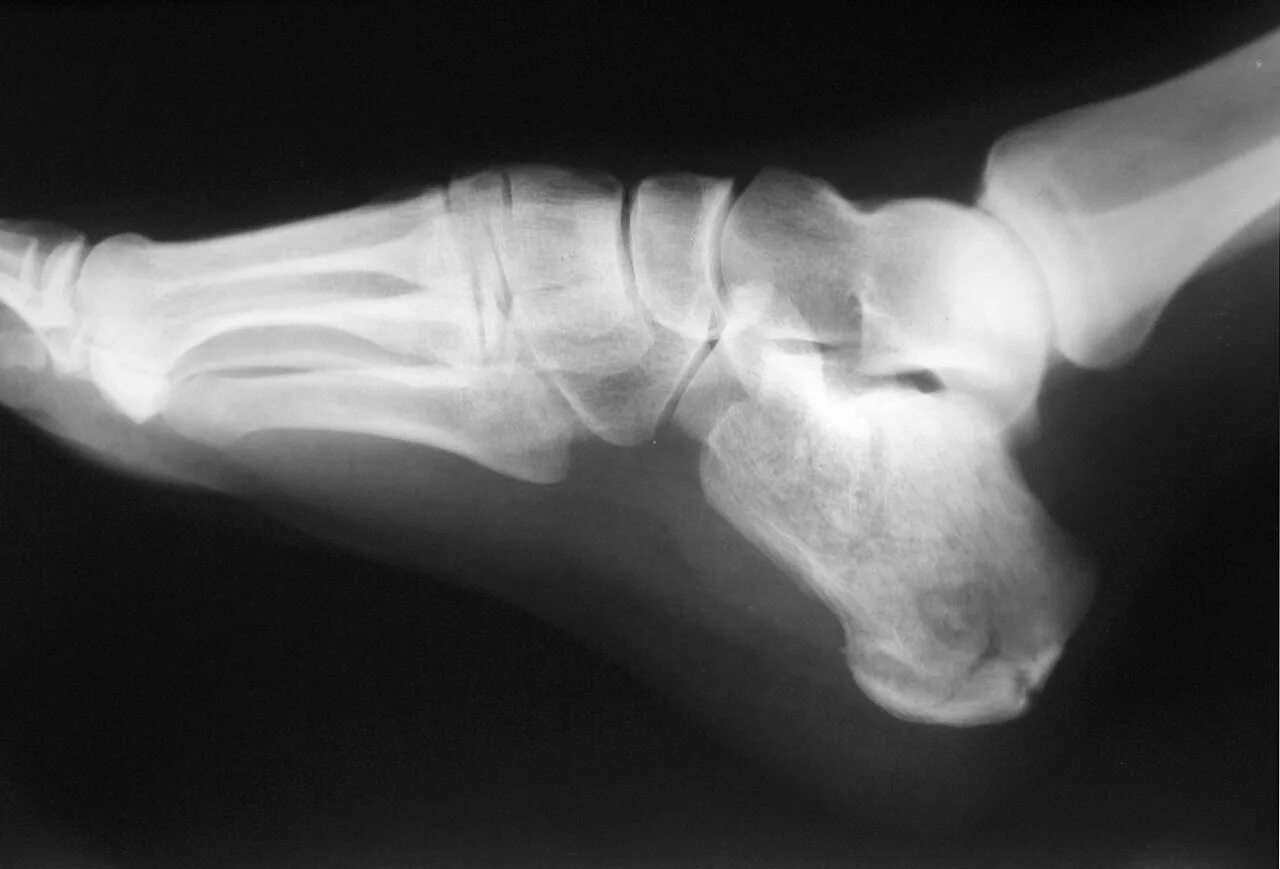

Пяточный перелом без смещения